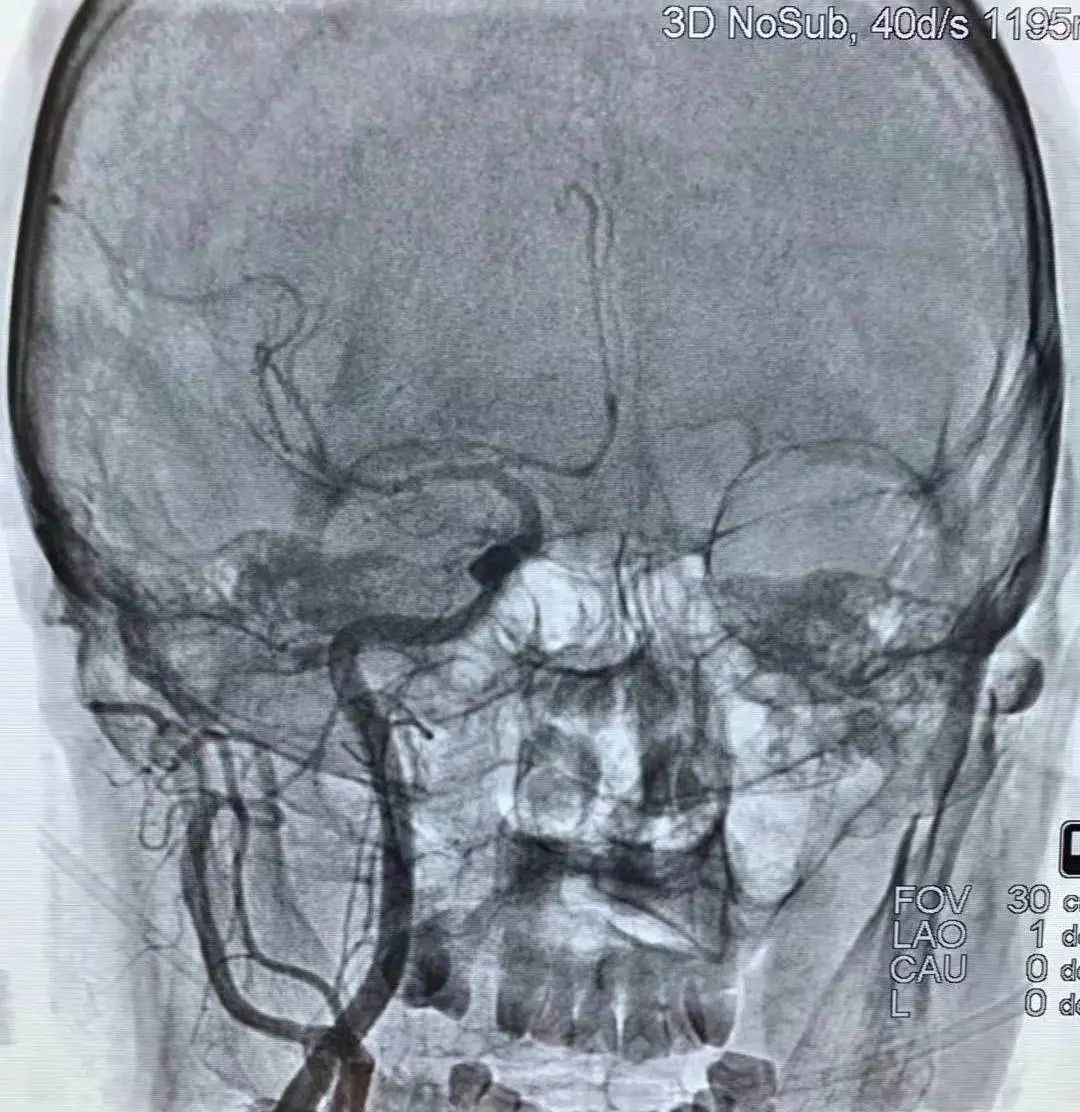

血管内的治疗还包括血管狭窄的治疗,在做头颅磁共振或脑血管造影时,如果发现有血管狭窄,医生就会建议放一个支架,这样就避免了脑梗塞的发生。

近年来,脑血管介入治疗显著提高了闭塞血管的开通率,为静脉溶栓失败和溶栓禁忌的大动脉闭塞患者提供了一种新的治疗选择。但具体诊疗过程中还要因病施治,要根据病人的病情决定什么样的治疗。